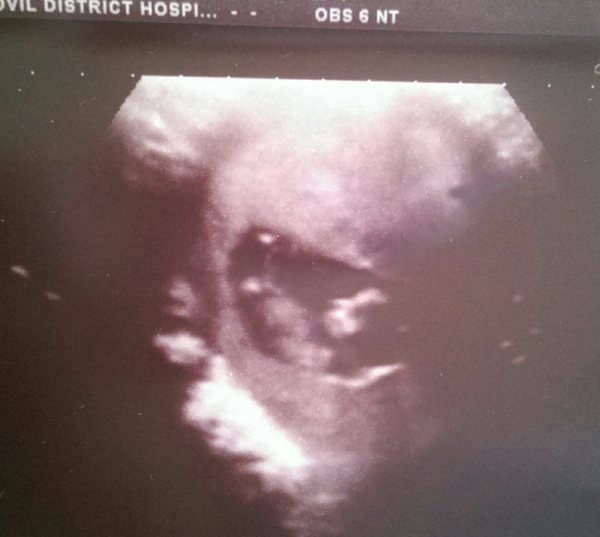

Oh! And here's bean...

Jan 2016 #4 - heading for the end of the 1st trimester with dating scans and wacky dreams

Well I'm the opposite of you crumble. Had my 12wk scan earlier (calculated from ovulation that I should be 11+5). Bean only measured in at 10+4! I asked if that was a worry, I.e. devoloping slowly, but they said they weren't worried at all considering how active bean looked. Wiggling and bucking about and heart was strong going like the clappers.

I knew implantation could be a while after ovulation but not that long! They said it's not uncommon. It could be a case of a lazy egg or slow swimmers (or bit of both).

Main thing is bean is happy and well! Just stepped back a week. Have to go back for another scan for NT screen as too small now.

So stats update, New EDD 15th Jan, though they don't want to give me one for def until my actual 12wk scan on 3rd July.